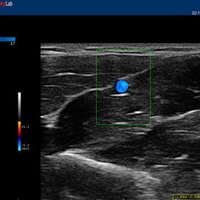

• Features: Farb/Doppler, Nadelführung, SW/B-Bild

Welches Baujahr ist das Esaote MyLabOne?2009 In welchem Zustand war das Esaote MyLabOne, als Sie es gekauft haben?Refurbished Welche Ultraschallverfahren nutzen Sie mit dem Esaote MyLabOne? 2D, Duplex Wie würden Sie die Bildqualität des Esaote MyLabOne bewerten? Sehr gute detailreiche Auflösung und Kontrast Wie bewerten Sie das Preis-Leistungsverhältnis des Esaote MyLabOne bewerten? Kein Fehlkauf Bitte beschreiben Sie in einem Satz, Ihre Erfahrungen mit dem Esaote MyLabOne. Sehr gutes High-End Gerät. Bei wem haben Sie Ihr Esaote MyLabOne gekauft? Esaote Hersteller Wie viel haben Sie damals für das Esaote MyLabOn ein Euro gezahlt? (Bitte geben Sie den Wert ohne Punkt und Komma an) 4000€ Beinhaltet der Kaufpreis einen Servicevertrag?Nein